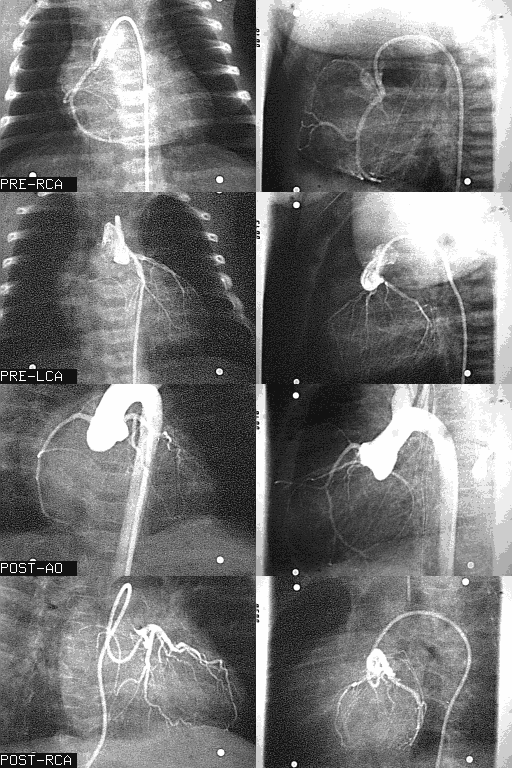

Arterial Switch Operation: Source Angiograms